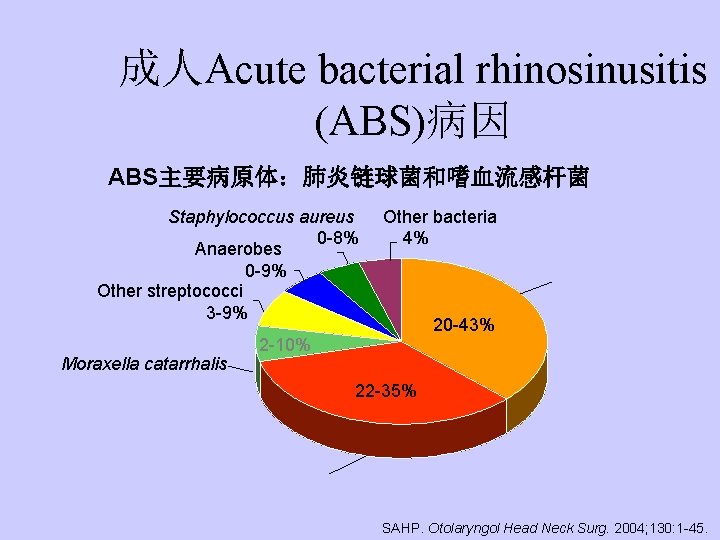

成人Acute bacterial rhinosinusitis (ABS)病因 ABS主要病原体:肺炎链球菌和嗜血流感杆菌 Staphylococcus aureus 0 -8% Anaerobes 0 -9% Other streptococci 3 -9% Moraxella catarrhalis Other bacteria 4% S. pneumoniae 20 -43% 2 -10% 22 -35% H. influenzae SAHP. Otolaryngol Head Neck Surg. 2004; 130: 1 -45.